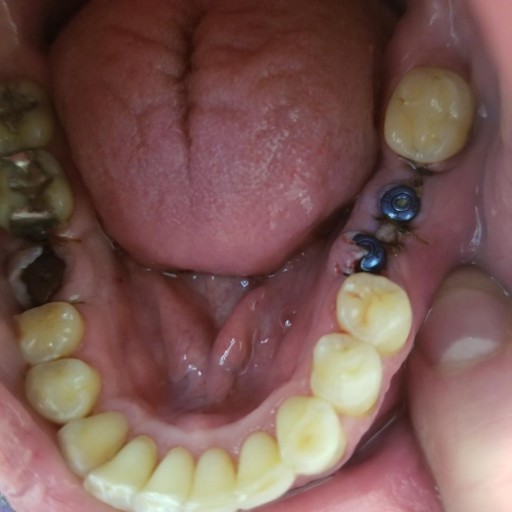

Three weeks ago i had an implant placed in my mouth on tooth #30 on the right side of my lower jaw. Unfortunaltely my dentist drilled to far with the implant prep drill and nicked the inferior alveolar nerve. I felt a electric shock sensation when this happened and he immedialtey back it off. He then proceeded to extract tooth #31. The roots of that tooth were very close to the nerve canal but he feels the injury occurred with the implant drill. I now have altered sensation and numbness on my lower lip, chin as well as gums and teeth. My dentist informed me that nerves heal slow and this might take weeks months or even a year. He cant even guarantee ill ever get feeling back. The tightness in my lower right teeth is the hardest thing to deal with right now. I feel a lot of pressure and tightness there. Ibuprofen is helping somewhat. > > My current dilemma is trying to decide whether or not to remove the existing implant that he was then able to install. We confirmed the next day by 3d Cone Beam scan that the implant he installed is not violating the nerve canal so his recommendation was to leave it in. I would rather leave it in and not risk causing more damage to an already injured nerve. The confusing part is when i got a second opinion from a different dentist he advised me to take the implant out. He did not even want to see any imaging or film. My question is if its not violating the nerve canal what is the harm in leaving it in? He acknowledge that there is no physical impingement to the nerve from the implant but wont elaborate further about why to remove it. I just don't know whether to leave it in or take it out. Is it possible that the tightness i fell in my teeth is a result of the implant or the initial nerve damage itself? I just want to make sure i do the right thing and give myself the best opportunity to heal. Its been a real challenge coping with this. I'm having a hard time finding someone with expertise with this type of injury. Any guidance you can give me would be greatly appreciated. > Thank you > Mike Perkin

I had 3 implants done yesterday, with 2 that were next to each other (see picture). One is not aligned. I am also doing ortho care and went in today to have a new retainer fitted. The dentist said he did not want to do new impressions due to the...